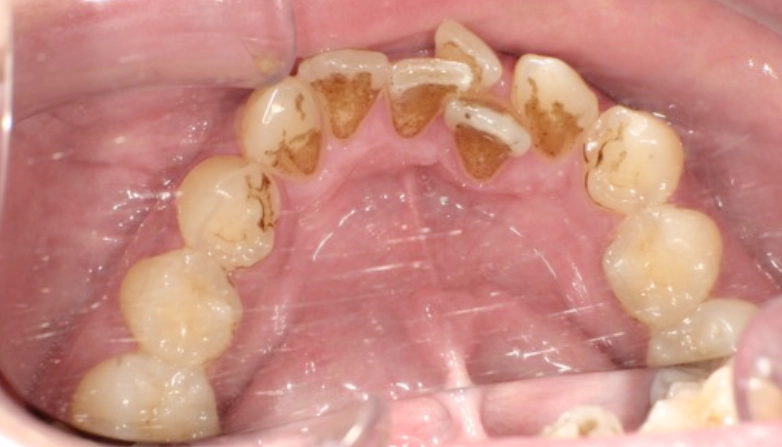

症例3

before

after

| 主 訴 | 着色を落としたい |

| 治療期間 | 通院 1回 |

| 治 療 費 | 1回 7,700〜11,000円(税込) |

| 治療内容 | PMTC |

| 治療のリスク | 歯自体の色を白くすることはできない。 しばらくすると再び着色することがある。 |